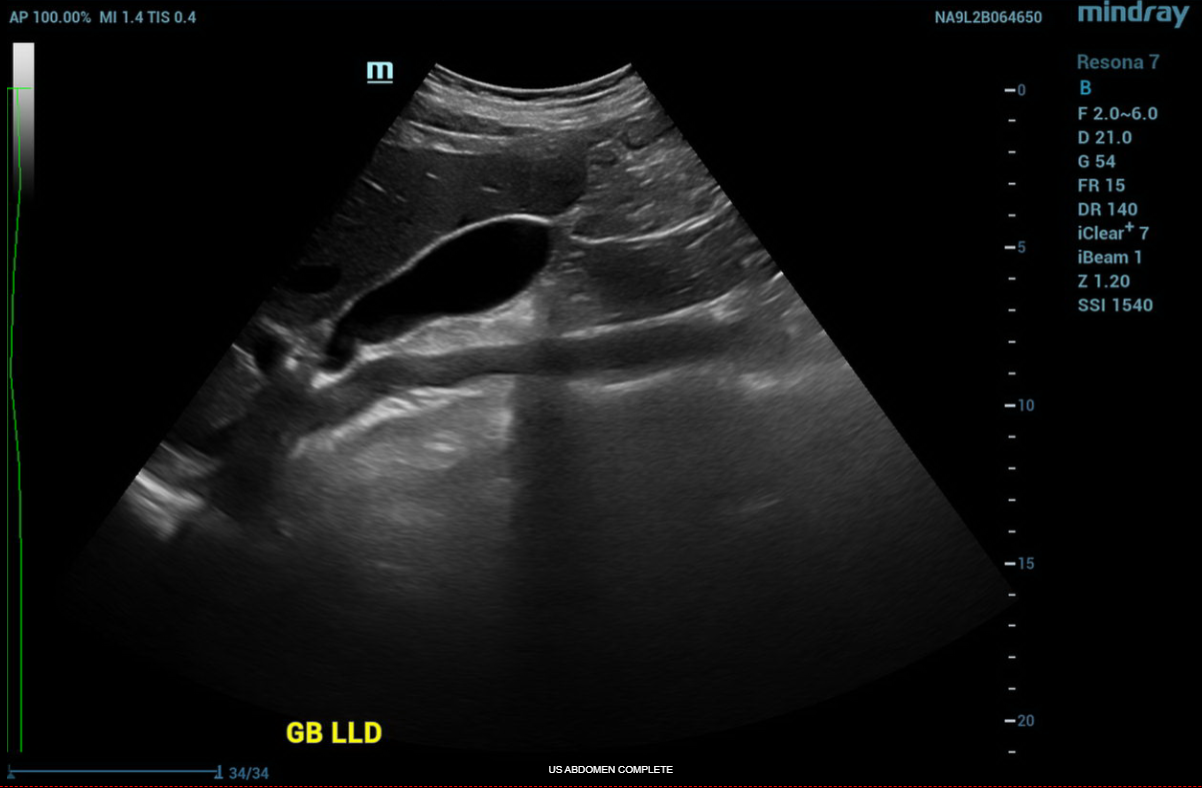

ULTRASOUND ABDOMEN GENERAL